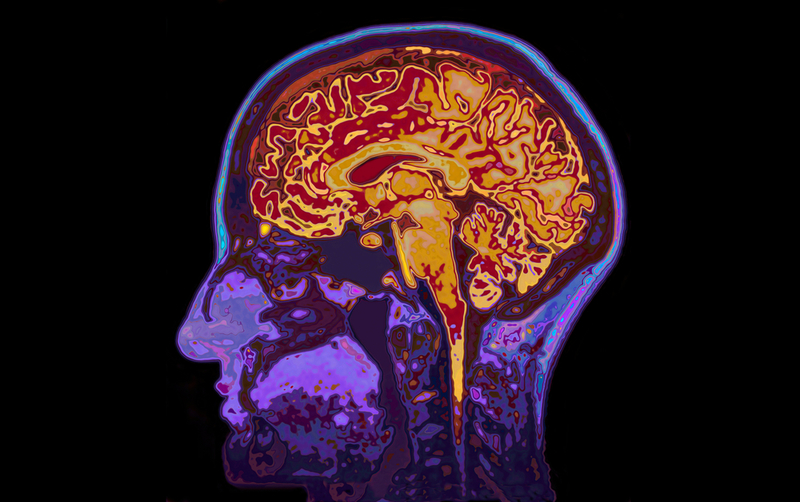

Researchers at the Massachusetts Institute of Technology (MIT) have devised a new magnetic resonance imaging (MRI) technique to image calcium activity deep in the brain.

Calcium is a critical signalling molecule for most cells, and it is especially important in neurons. Using the non-invasive technique, the researchers can track signalling processes inside the neurons of living animals, enabling them to link neural activity with specific behaviours.

However, current imaging techniques can only penetrate a few millimetres into the brain. "The study describes the first MRI-based detection of intracellular calcium signalling, which is directly analogous to powerful optical approaches used widely in neuroscience but now enables such measurements to be performed in vivo in deep tissue," said Alan Jasanoff, Professor at MIT.

The new MRI sensor, described in the journal Nature Communications, can measure extracellular calcium concentrations. The team tested their sensor in rats by injecting it into the striatum, a region deep within the brain that is involved in planning movement and learning new behaviours.

Because this method directly measures signalling within cells, it can offer much more precise information about the location and timing of neuron activity than traditional functional MRI (fMRI), which measures blood flow in the brain. "This could be useful for figuring out how different structures in the brain work together to process stimuli or coordinate behaviour," Jasanoff noted.